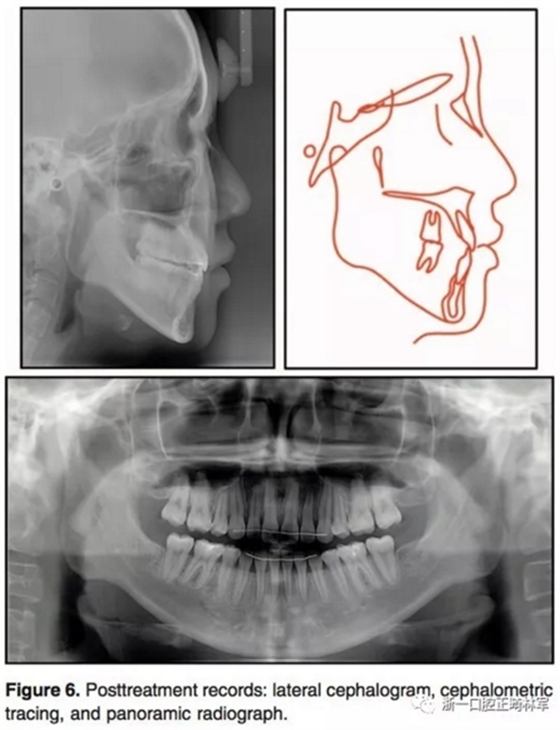

治療后結(jié)果示,治療目標達成。側(cè)貌改善。唇可以完全閉合,獲得了美學微笑(圖5)。全景示間隙關(guān)閉,牙根平行度可,未見明顯吸收。側(cè)位片分析和重疊像分析示上前后牙分別壓入2.8mm和1.9mm。下前后牙分別壓入4.2mm和1.4mm。上下頜前牙用最大支抗內(nèi)收。雙牙弓壓入后,下頜發(fā)生了逆時針旋轉(zhuǎn)(2.1°)??和頦前點前移(3mm)。